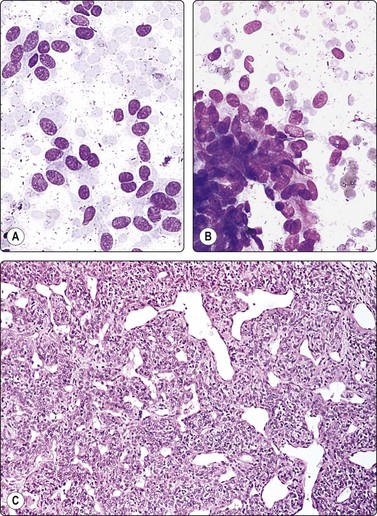

Wilms’ tumor (Figs 12.27 and 12.28)103-105

image

Fig. 12.27 Wilms’ tumor

Biphasic tumor; cohesive tubular structure and undifferentiated mesenchymal cells (MGG, HP).

Fig. 12.28 Wilms’ tumor

Small round cell tumor pattern of undifferentiated blastema (A, MGG; B, Pap, HP).

Criteria for diagnosis

Numerous undifferentiated small cells, single and in tight clusters (blastema),

Small, round or ovoid, hyperchromatic nuclei; multiple small nucleoli,

Scanty cytoplasm,

Epithelial differentiation: rosettes, tubular structures or cords (commonly present),

Mesenchymal differentiation: spindle cells (sometimes present).

Wilms’ tumor (nephroblastoma) is predominantly a tumor of childhood and is dealt with in more detail in Chapter 17. However, it can also occur in adults. Smears are usually dominated by small, undifferentiated malignant cells representing blastema. A specific diagnosis requires in addition evidence of epithelial and mesenchymal differentiation, but this may only be obvious in the better-differentiated tumors. Individual cells generally appear undifferentiated. Epithelial differentiation is suggested by microarchitectural patterns such as rosettes, tubules or cords (Fig. 12.27), which are not always present in smears. Correlation with clinical and radiological findings is important. The diagnosis may be supported by ancillary studies. The results of immunostaining are variable, depending on differentiation. Useful markers are vimentin, LMWCK, EMA and WT1. Heterogeneous cytogenetic abnormalities can be demonstrated in a proportion of tumors.